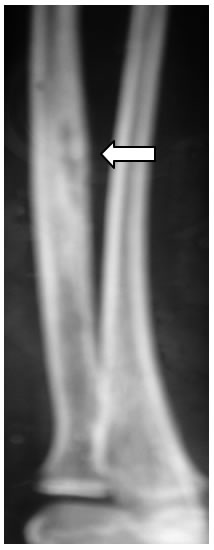

Alla discussione collegiale con radiologo e ortopedico peraltro questo non basta (a fronte di un quadro monofocale, progressivo) e si decide comunque di eseguire una TAC per la migliore definizione sull'osso. La TAC evidenzia, come atteso, un quadro di flogosi cronica con esuberante apposizione ossea periostale associata a modesta reazione ossea endostale (figura 4), senza lesioni suggestive di tumore.

Figura

4: la TC, eseguita senza mezzo di contrasto, conferma l'importante

reazione periostale (

) e mostra una discreta reazione endostale (

).